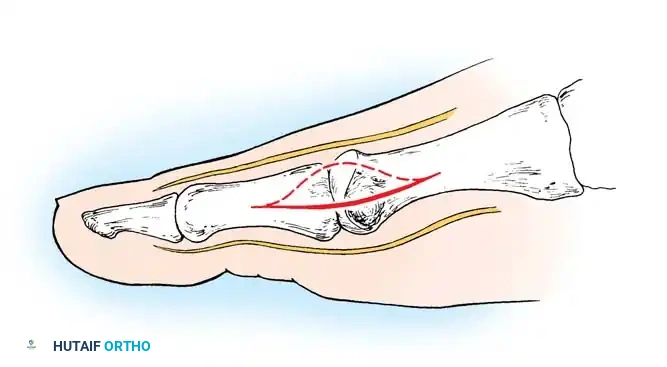

• Make a longitudinal capsular incision (the original McBride capsular incision was transverse) 3 to 4 mm plantar to the line of the skin incision (Fig. 78-14).

Fig. 78-14 Modifi ed McBride procedure. Longitudinal capsular incision is 3 to 4 mm plantar to skin incision.